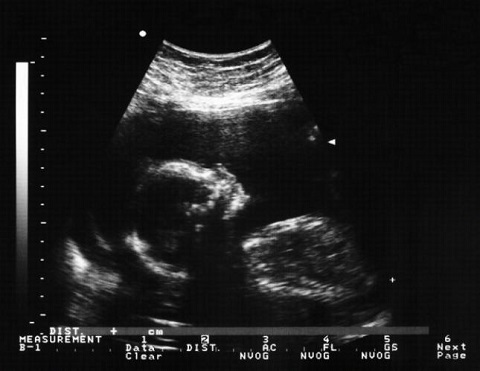

#2 Manipulación genética prenatal

Este es uno de los más polémicos de la lista. La posibilidad de modificar genéticamente los embriones para evitar el desarrollo de ciertas mutaciones que den lugar a enfermedades fatales o invalidantes es algo interesante y los científicos creen que es un área de la ciencia que tendrá un gran desarrollo en los próximos cinco a diez años. Esta tecnología podría ser bien utilizada para prevenir enfermedades y salvar muchas vidas, sin embargo, se enfrenta a un dilema moral inevitable: ¿hasta qué punto se puede manipular la vida? Indudablemente, una discusión que habrá que dar en el futuro.